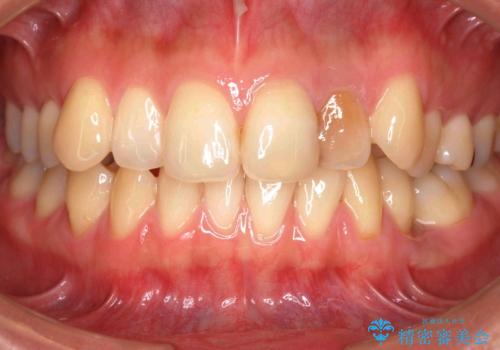

- 前歯のがたつきと左下の歯がうまっているとのことで、矯正治療を希望されました。

また、左上の変色した前歯はセラミックでやりかえを行なっています。